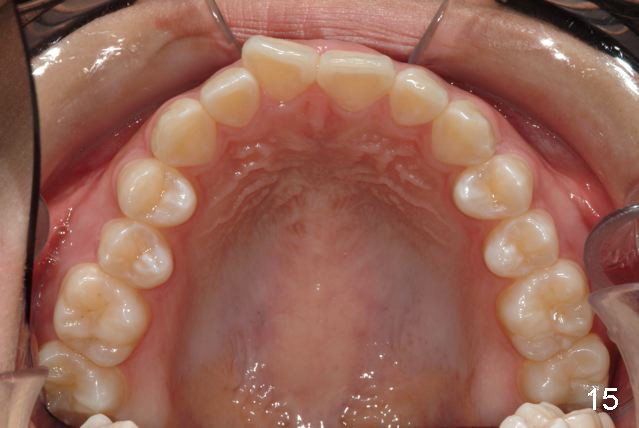

Answer: I was afraid tooth #8 would try to rotate (Fig.).  I do not like U bonded retainers as much as lower but I thought maybe in this case due to #8 initial position.  I have provided 2 removable retainers to fit over for insurance!